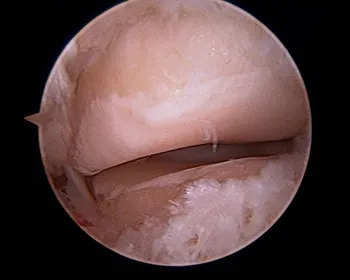

Intraoperative subtalar joint arthroscopy pics

Scar tissue and fibrous band in the subtalar joint

Cleaning out the joint